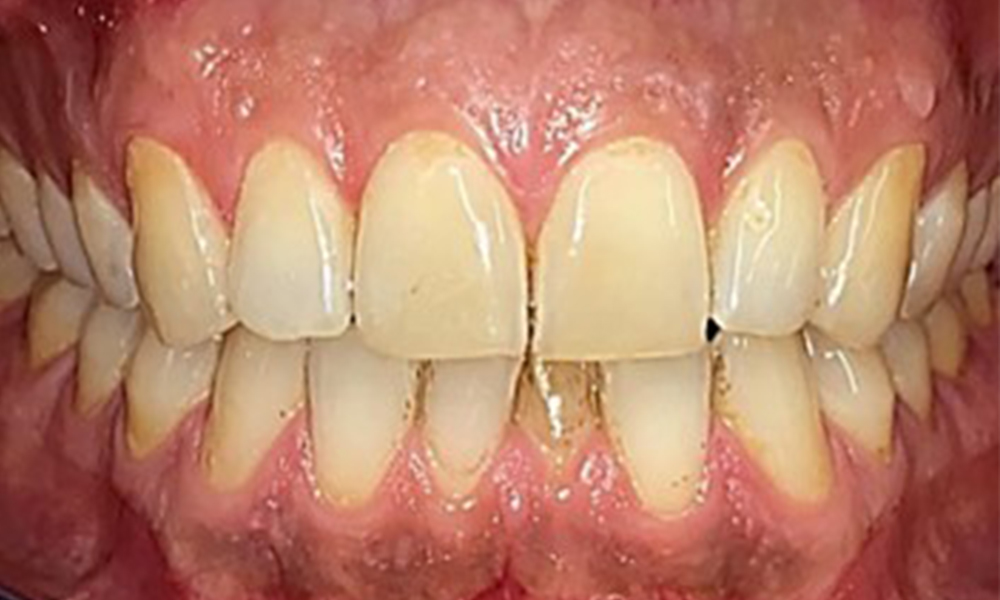

There were no pathological extraoral findings. During intraoral examination, inspection of the frontal view revealed brownish discolouration near the keratinised gingiva and at the transition to the moveable mucosa (Fig. 2), which could be attributed to nicotine consumption. Whitish mucosal lesions were observed on the palate, particularly near the maxillary molar palatal surfaces, indicating increased keratinisation and can also be attributed to nicotine consumption. The tongue was covered with a removable white and brownish coating.